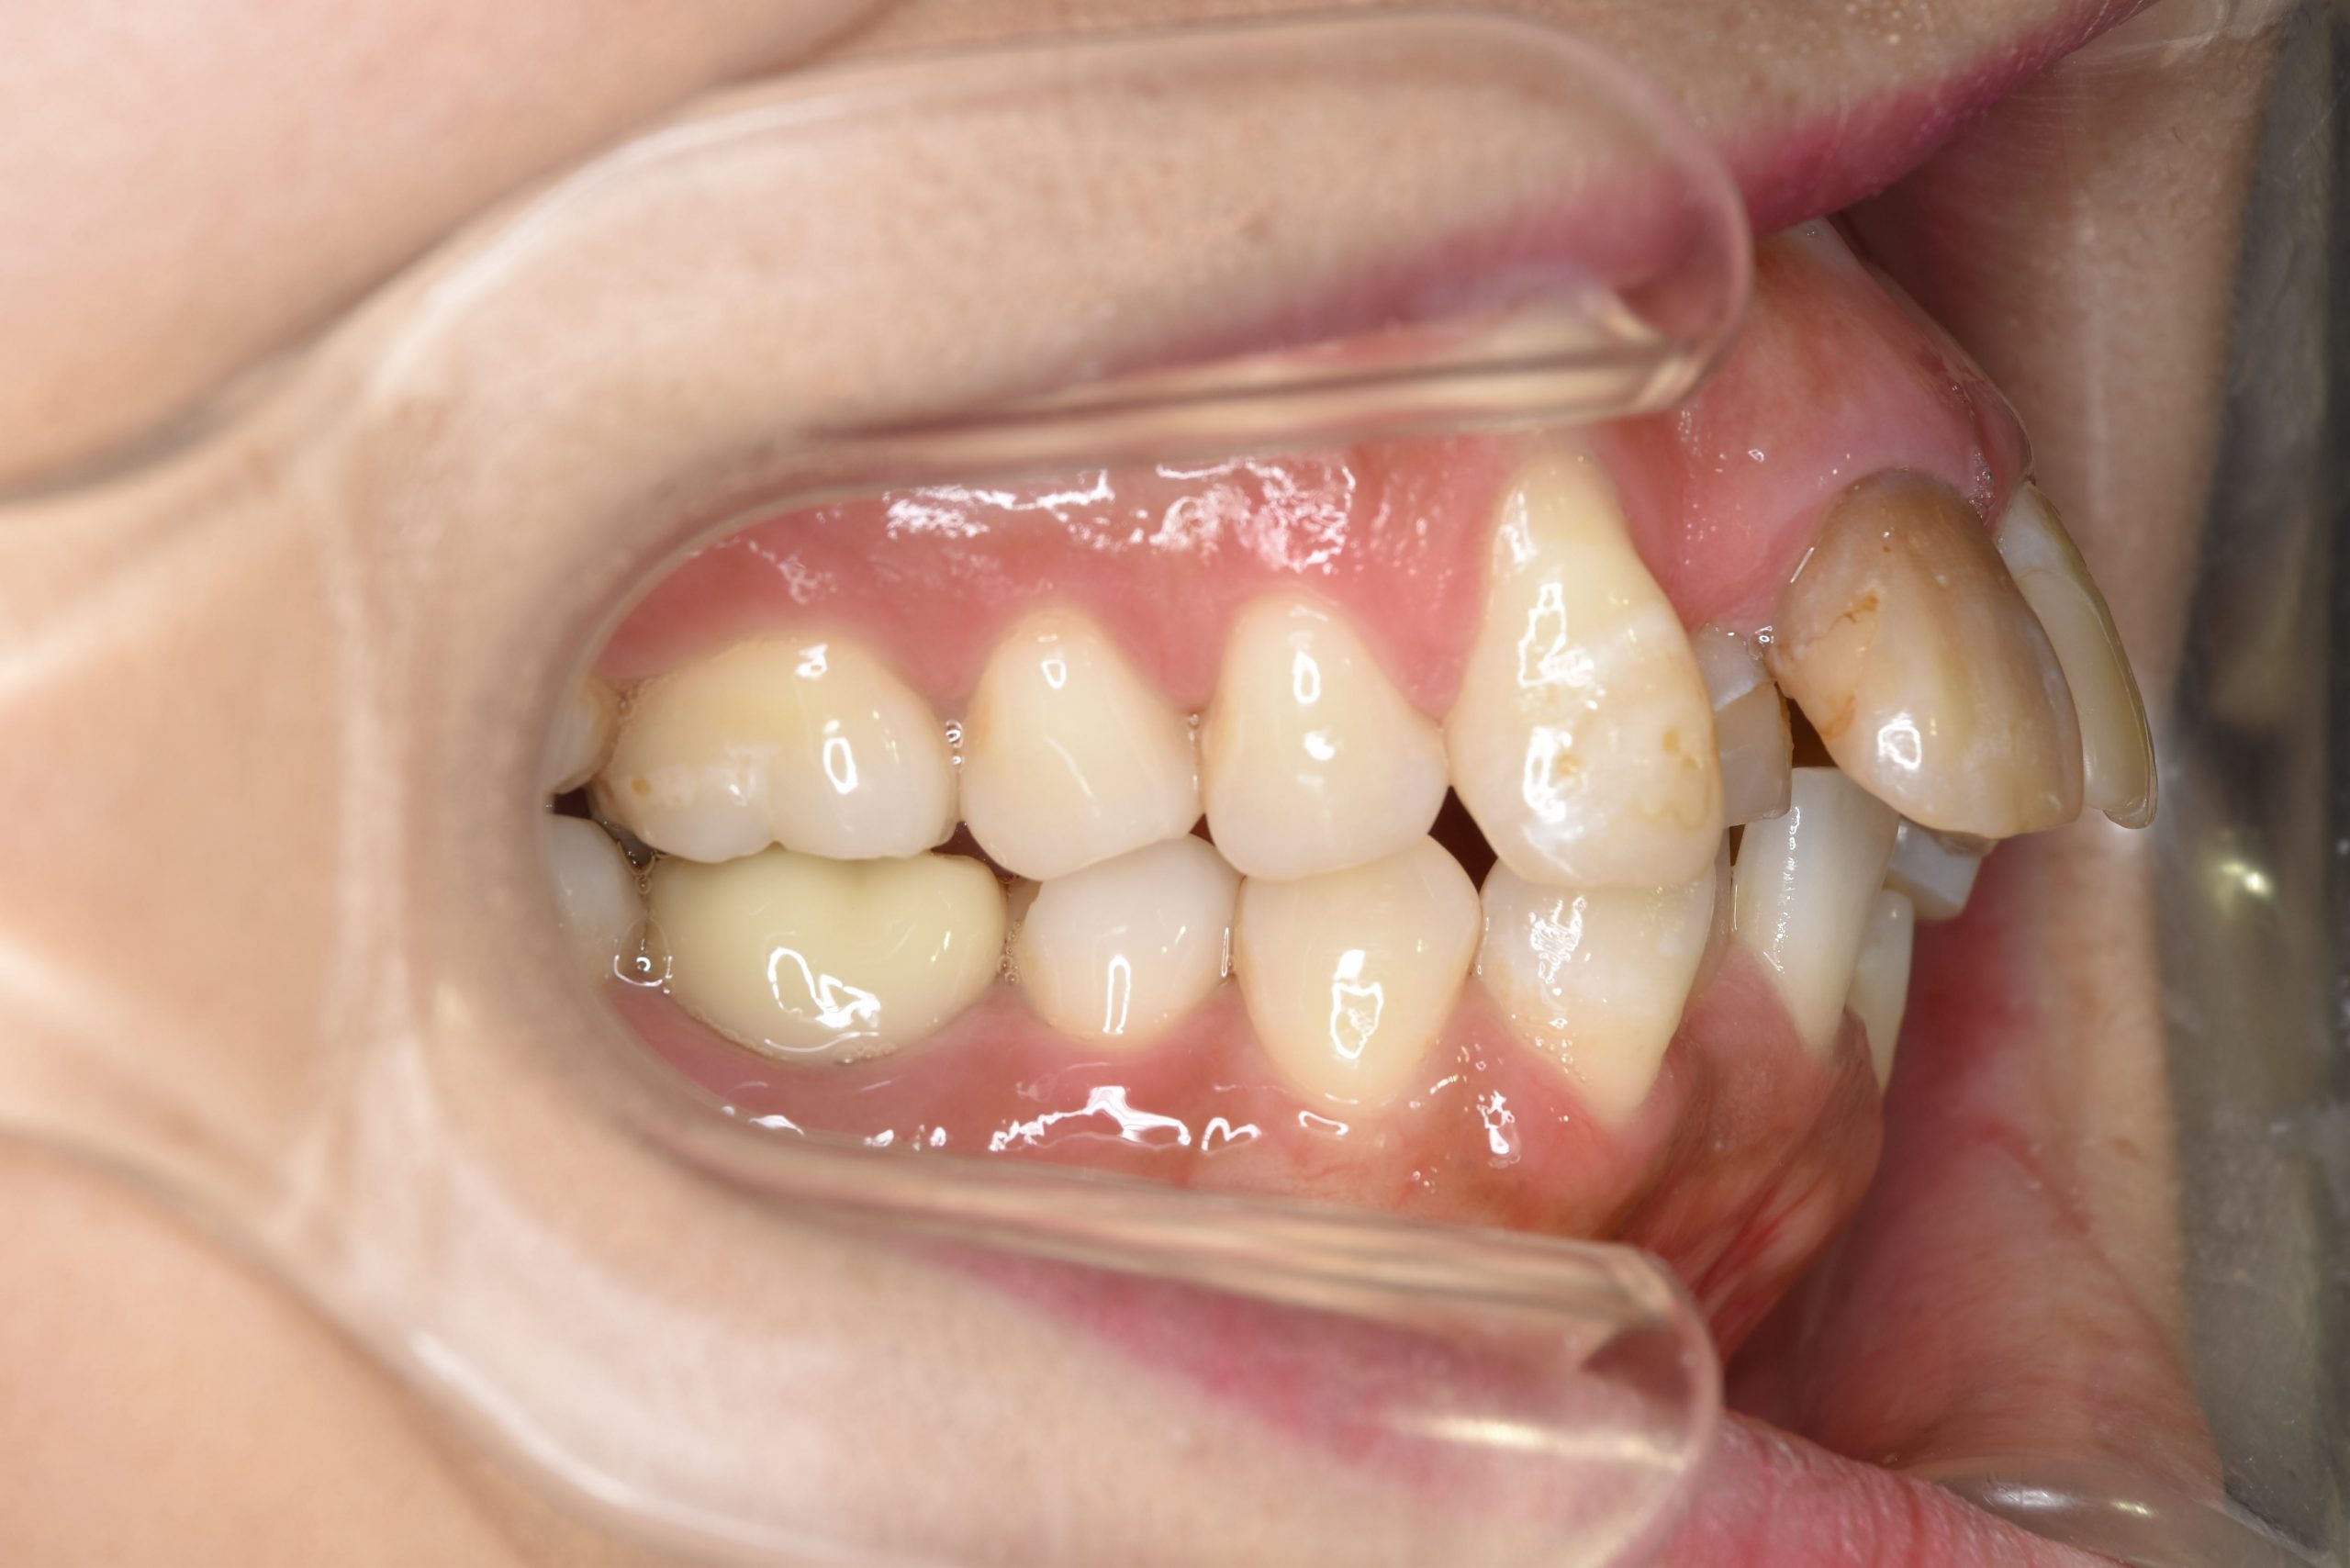

ビフォー

インビザライン矯正治療|症例_649